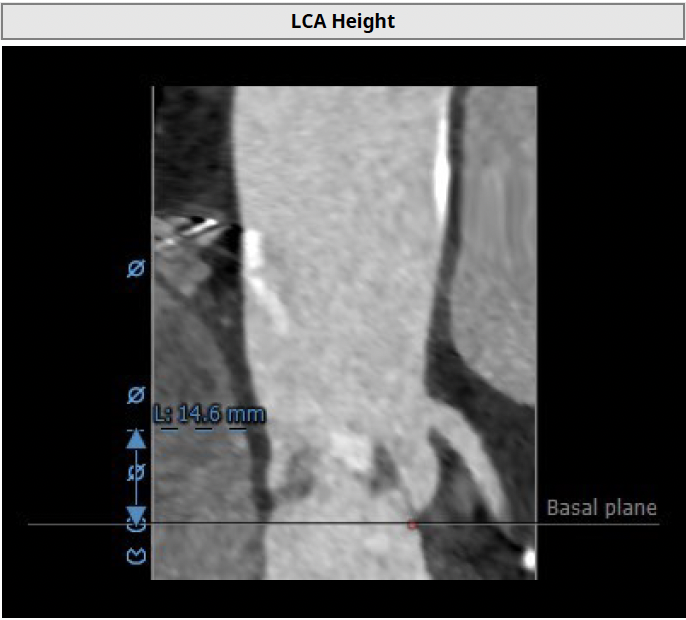

左冠高度高度:14.6mm